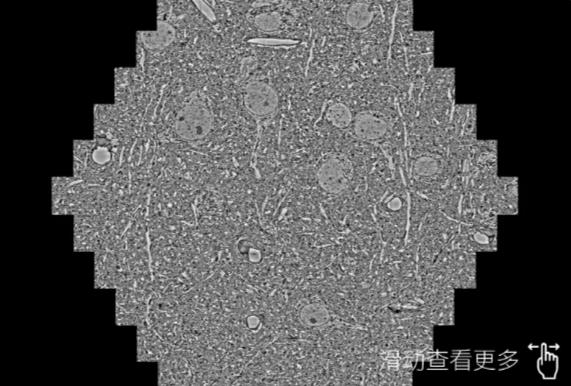

鼠脑切片。左图使用深圳蔡司深圳扫描电镜MultiSEM706对165μmx143pm面积区域成像,耗时仅需1.5秒。右图为鼠脑切片中30μm区域放大效果。样品由芝加哥大学B.Kasthuri提供。

使用蔡司高速深圳扫描电镜MultiSEM对1mm²人脑皮层组织进行高分辨成像,并对其中的各种细胞结构进行三维重构分析。左图展示了2x3mm²组织平面中锥体神经元的三维重构效果。右图显示了局部体积神经元三维重构。图像由哈佛大学chtman实验室提供,渲染图由D. Berger 制作。